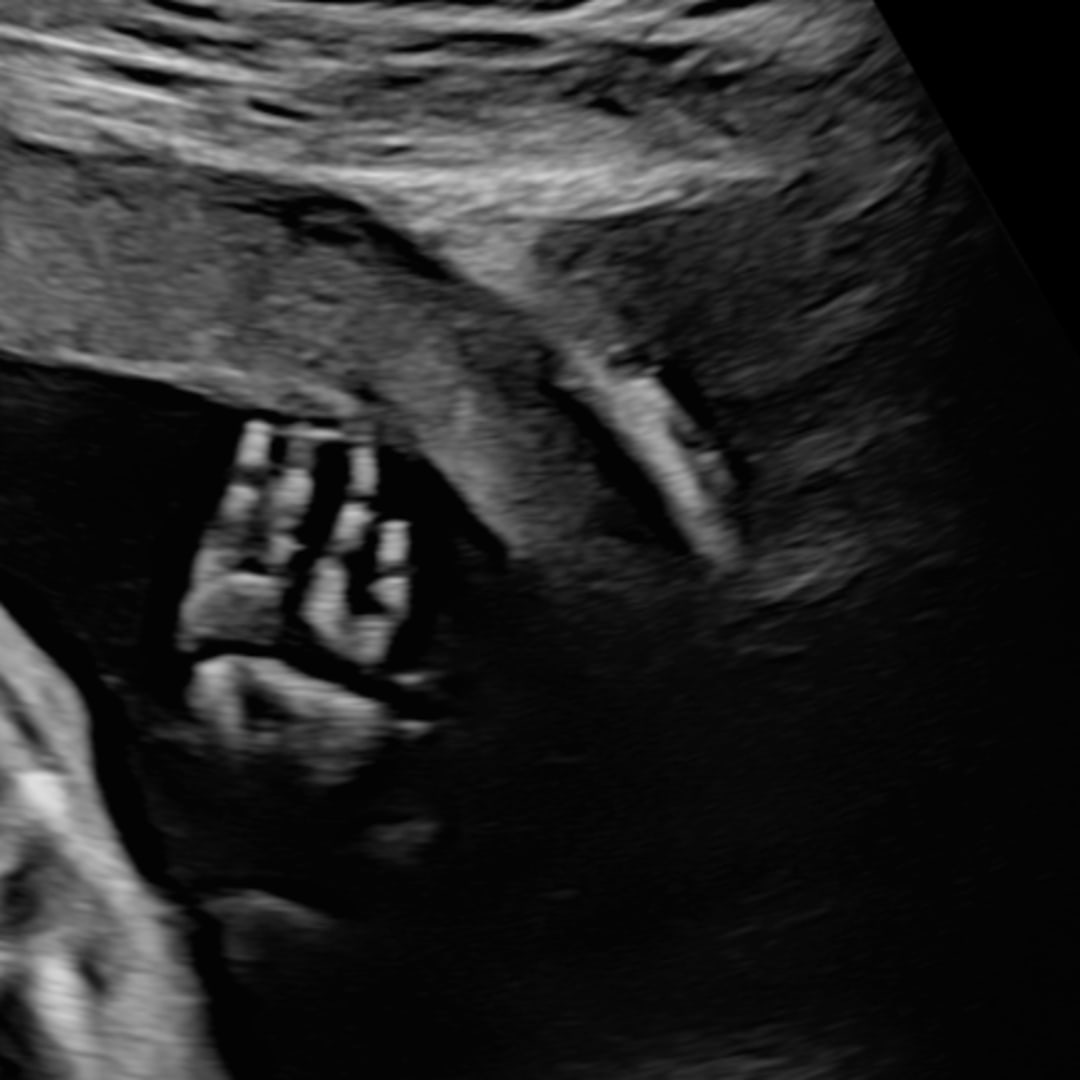

Baby Violet🩷🧸